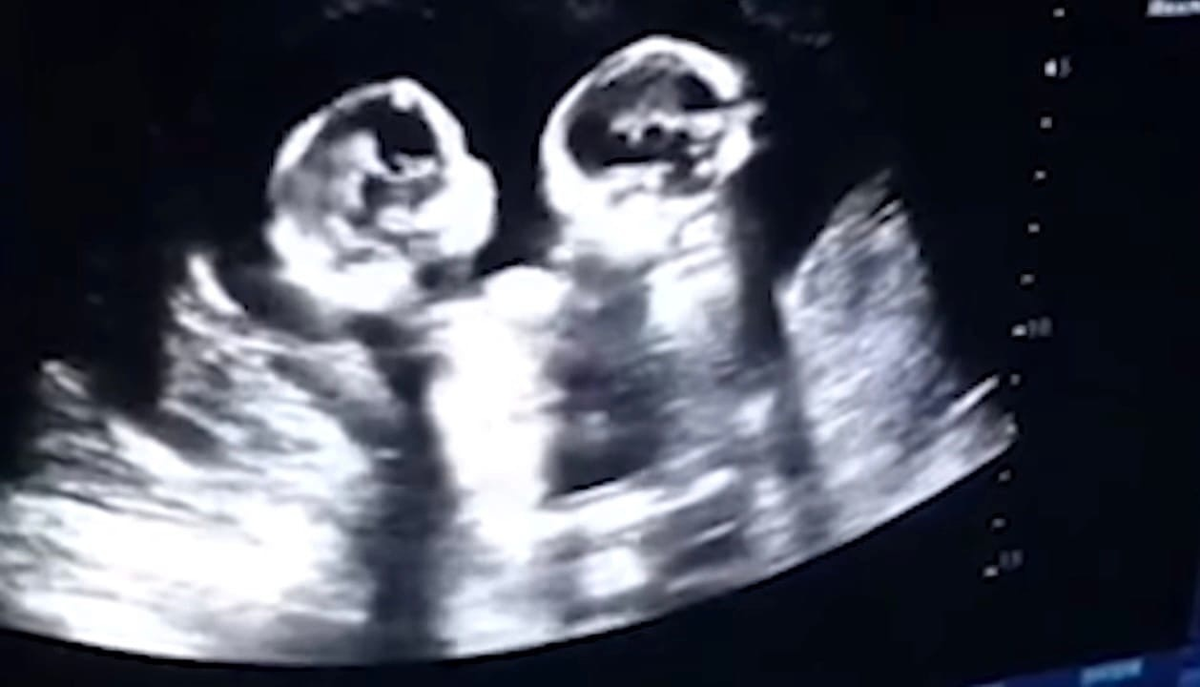

Ребенок исчез во время узи как называется